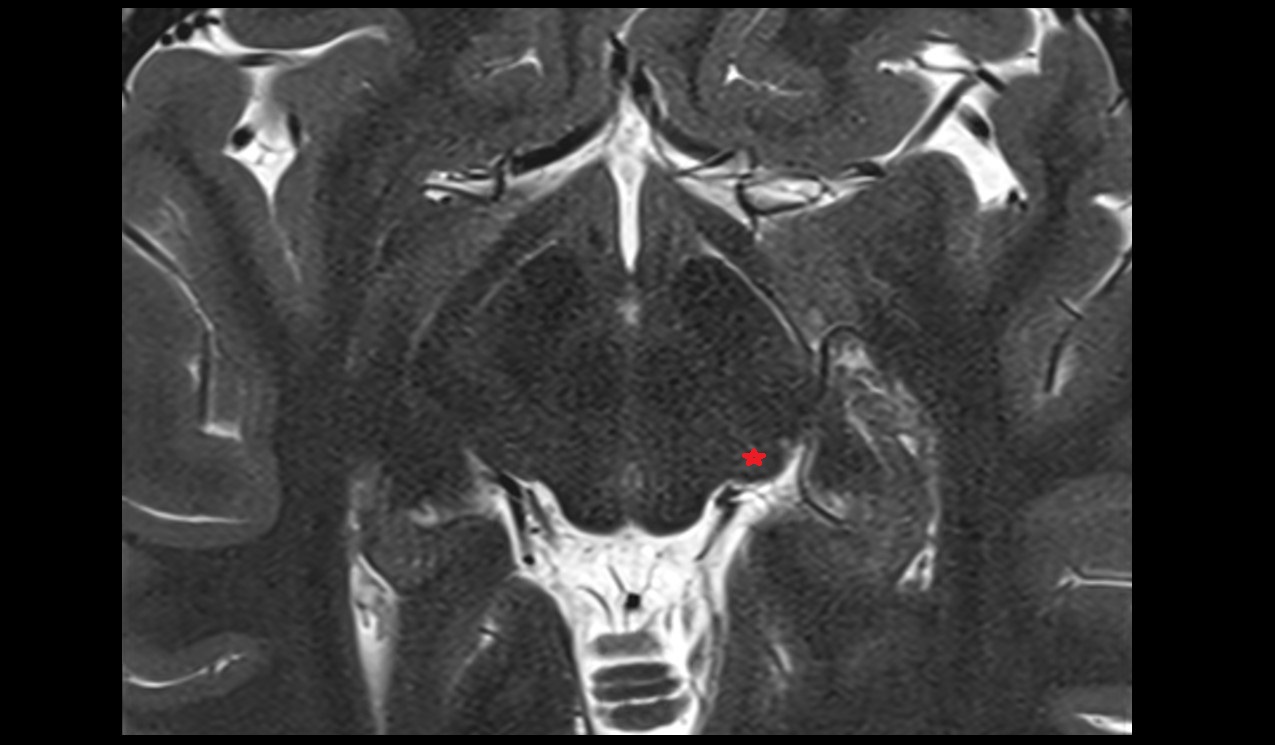

- Peripheral zone of prostate

- Anterior Fibromuscular Stroma of prostate

- Central zone of prostate

- Transitional zone of prostate